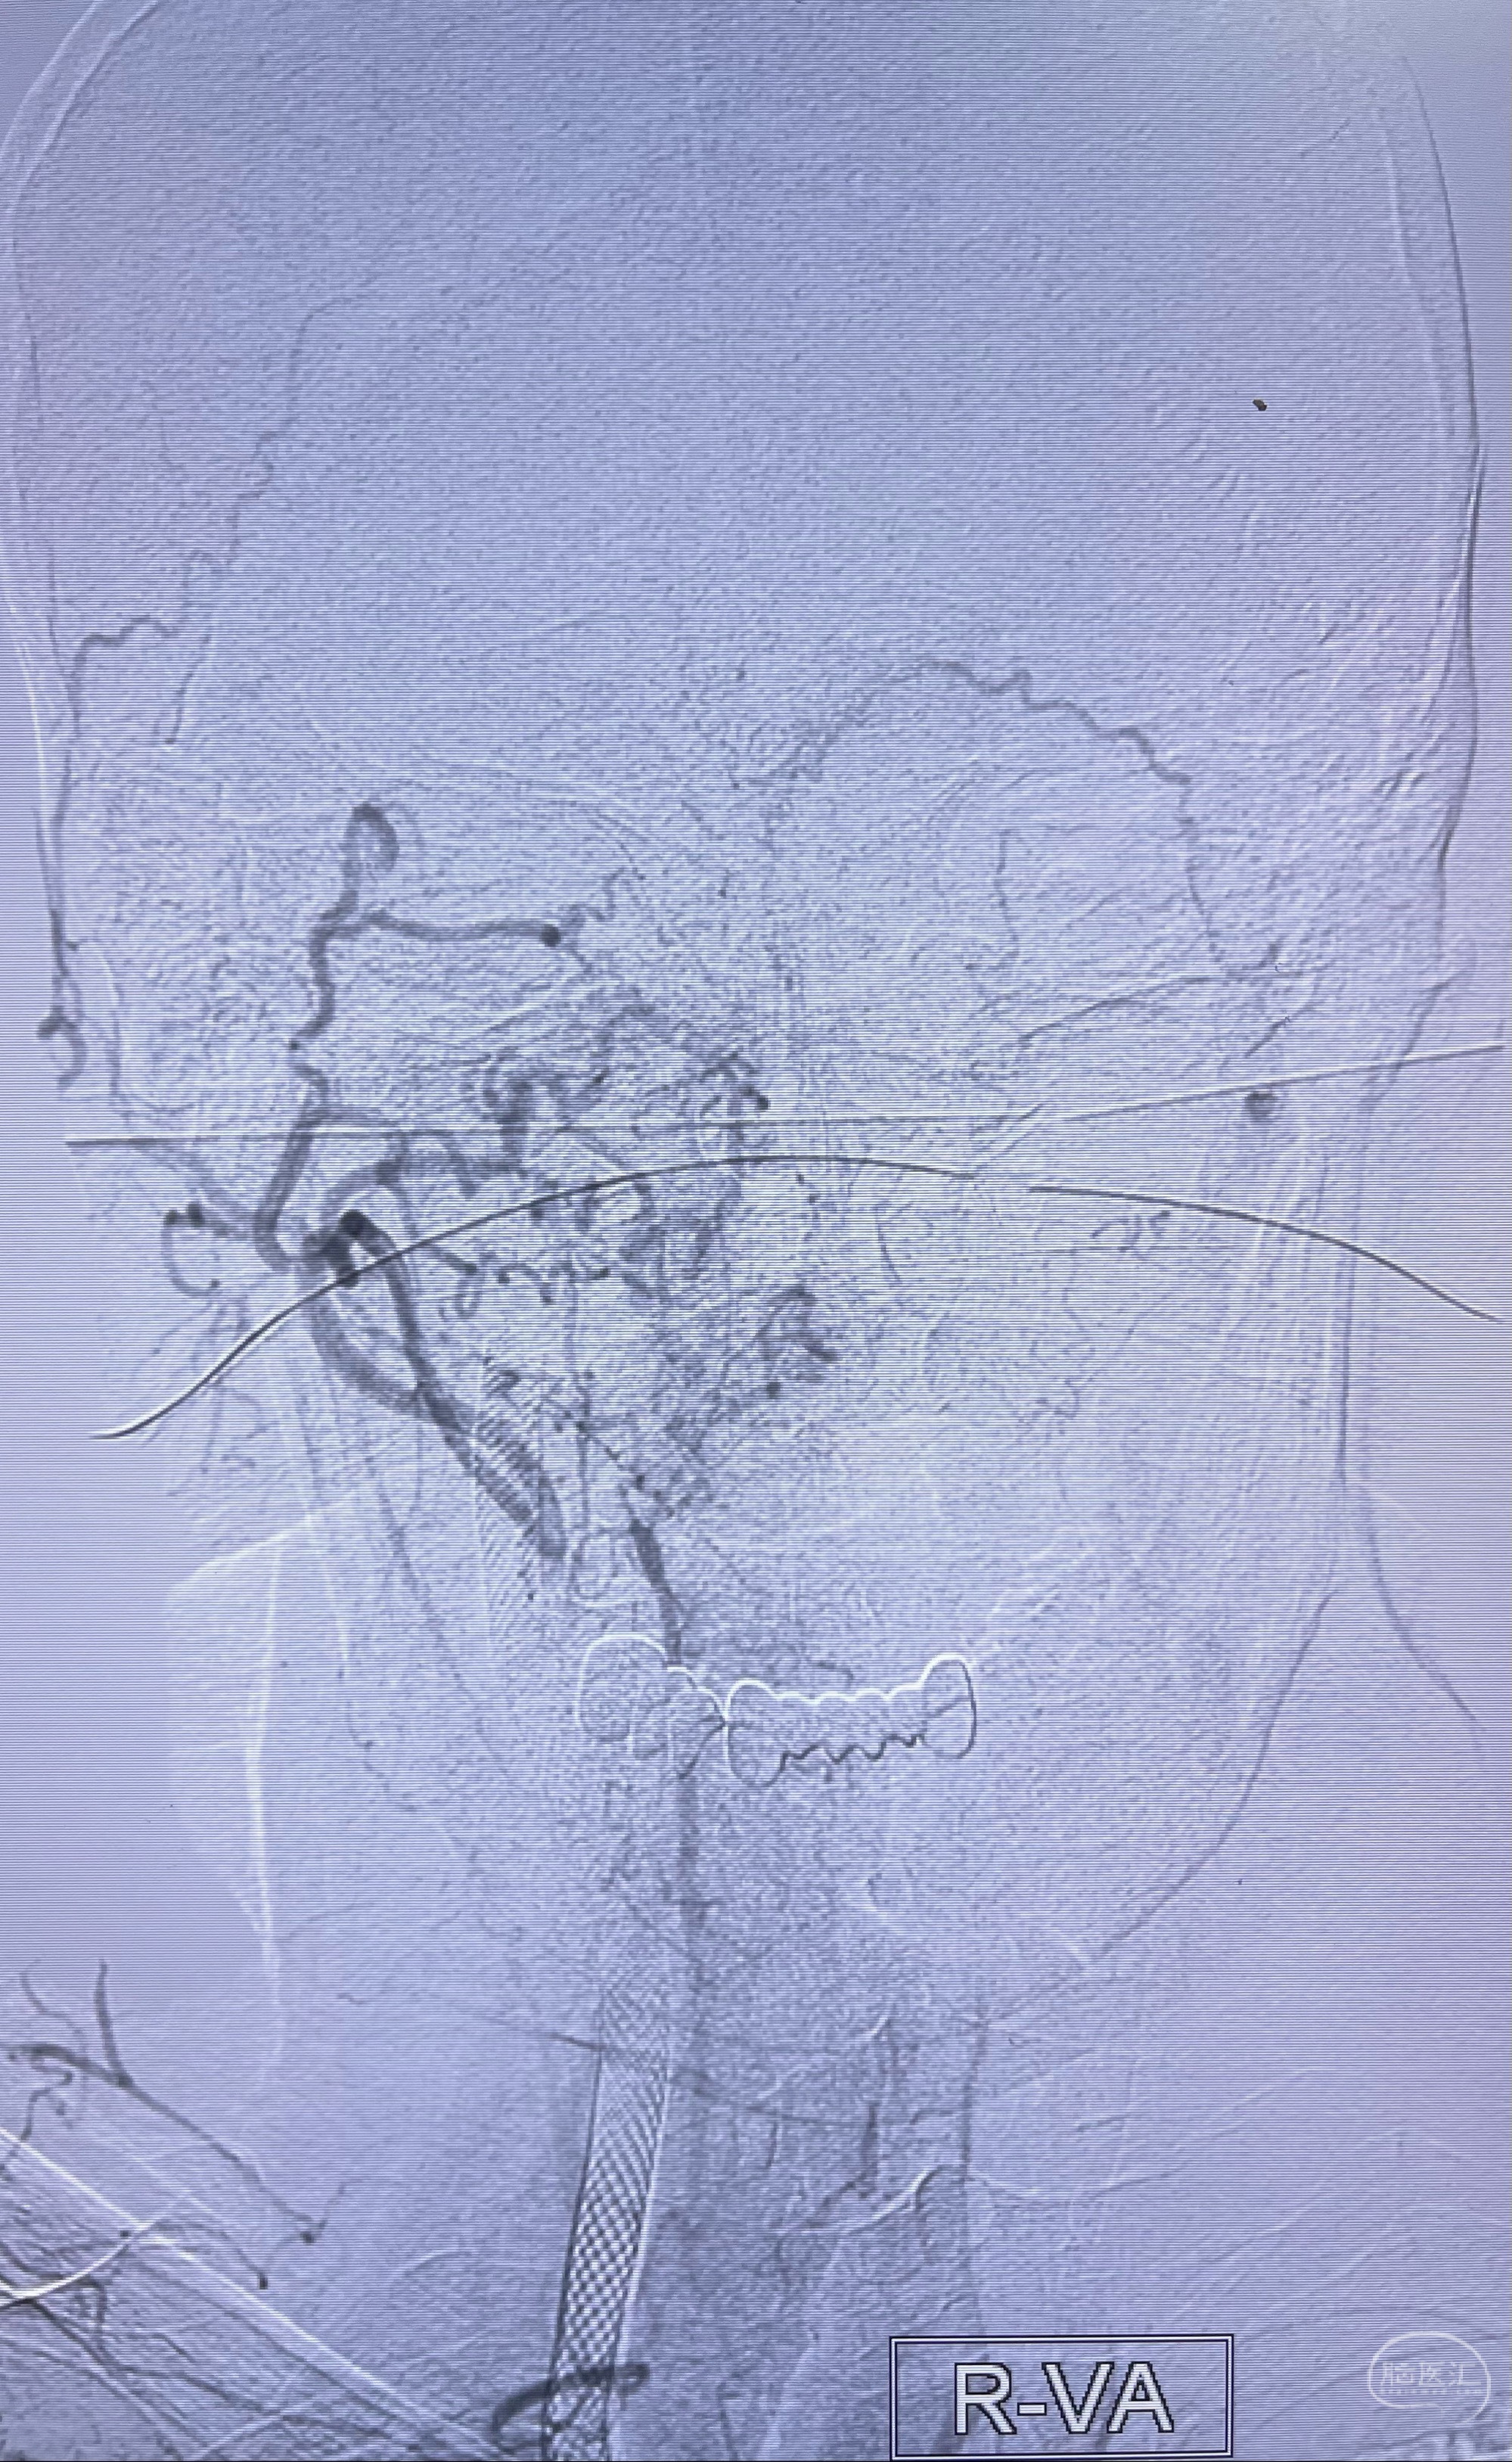

右侧椎动脉可见吻合代偿右侧颈外动脉

双抗准备后于2023-07-13在全麻下行右侧颈内动脉功能保护

重新行“路径图”,支架导管在微导丝引导下超选择性插入至右侧颈内动脉眼段,4.5-50mmLeo支架释放,远心端位于海绵窦段,近心端位于岩骨段狭窄段以近

即刻造影显示支架贴壁佳

支架完全打开,近心端位于原颈动脉支架远心端内

麻醉苏醒佳,遵嘱活动!